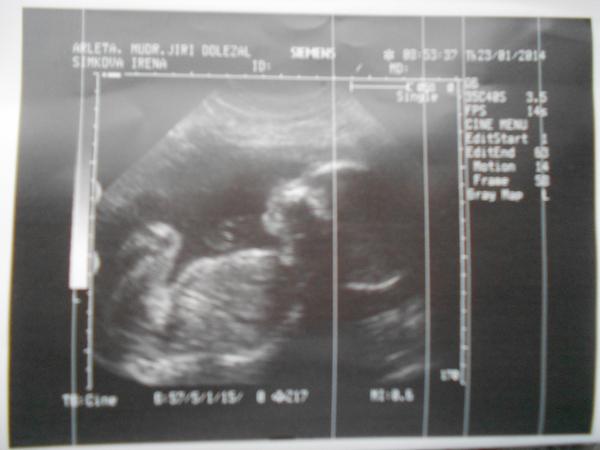

@sweetest jo jo už je to drobeček a vše je Ok 😉

Tak dnešná naša poradňa dopadla super, máme za sebou morfologický ultrazvuk , všetko je v poriadku, podľa PM sme 20+0 tt, podľa sona 20+3 tt a čakáme chlapčeka. 🙂